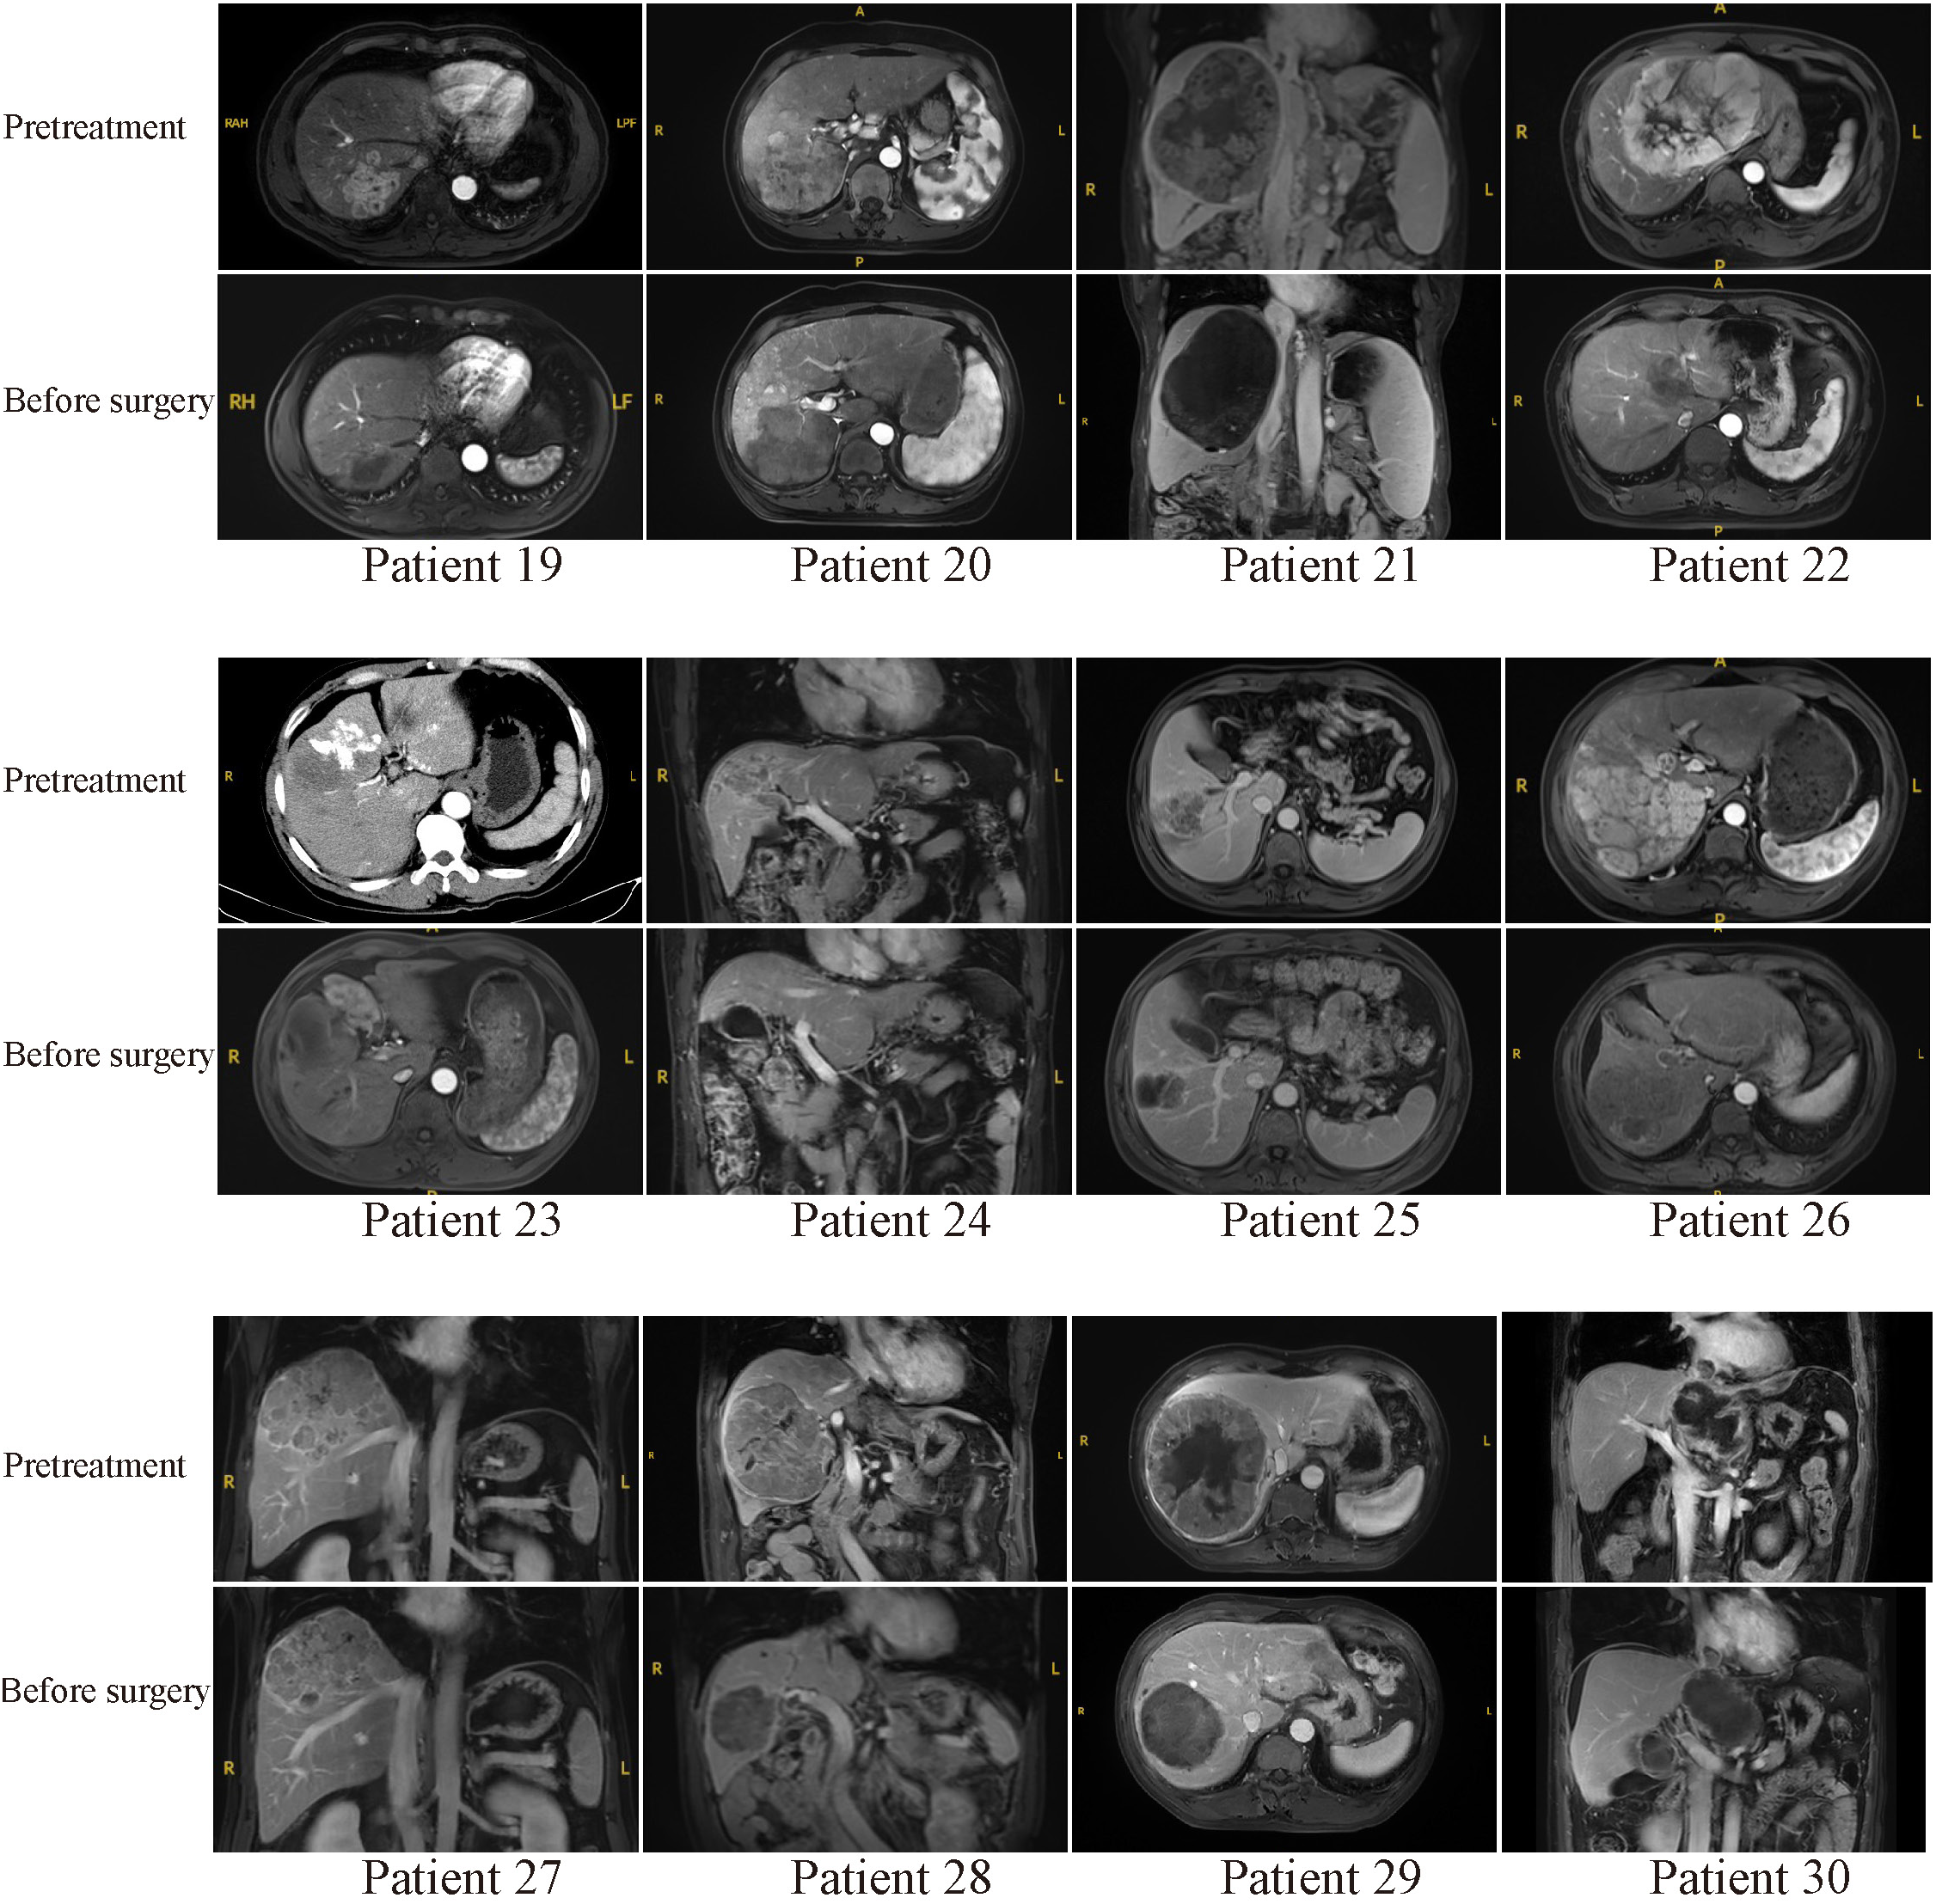

Typical MR or CT imaging scans of other patients (besides patients 8 and 17) before systemic treatment and before surgery were also listed in Figures 4, 5. The major reason for unresectability were tumor invasion into major portal vein (patients 12, 18 and 22) and the main branches of the portal vein (patients 2, 7, 9, 11, 14, 20, 24, 25, 26, 27 and 28), into hepatic vein or inferior vena cava (patients 5, 21, 29 and 30), into right hepatic bile duct (patient 3), multiple intrahepatic lesions (patients 1, 6, 15, 16, 19 and 23), insufficient remnant liver volume (patients 4 and 13), anatomical constraints for curative resection (patient 10), concomitant hilar or retroperitoneal lymph node metastasis (patients 7, 20 and 21). Obvious tumor regression was observed in all these cases before surgery.

Figure 5

Pretreatment and preoperative MR or CT scans of patients 19-30. Patient 23 received emergency hepatic arterial chemoembolization due to rupture of hepatocellular carcinoma in other hospital before combination therapy.